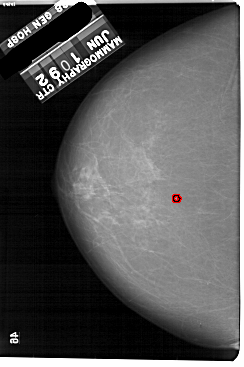

A_1864_1.LEFT_MLO

LEFT_MLO LINES 5491 PIXELS_PER_LINE 3316 BITS_PER_PIXEL 12 RESOLUTION 43.5 OVERLAY

FILE: A_1864_1.LEFT_MLO.OVERLAY

TOTAL_ABNORMALITIES 1

ABNORMALITY 1

LESION_TYPE CALCIFICATION TYPE PLEOMORPHIC DISTRIBUTION CLUSTERED

ASSESSMENT 4

SUBTLETY 2

PATHOLOGY BENIGN

TOTAL_OUTLINES 1

BOUNDARY